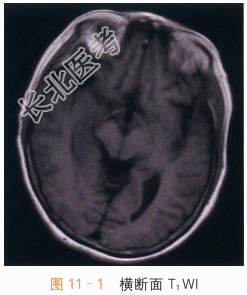

影像学资料如图11-1~图11-4所示。

读片分析:两侧岛叶及右侧颞叶可见片状异常信号影,右侧为著,呈T₁WI低信号,T₂WI、FLAIR高信号影,增强后可见轻度强化,未侵及两侧基底节区。两侧岛叶及右侧颞叶异常信号灶,右侧为著,结合患者临床表现及其它检查考虑病毒性脑炎可能。